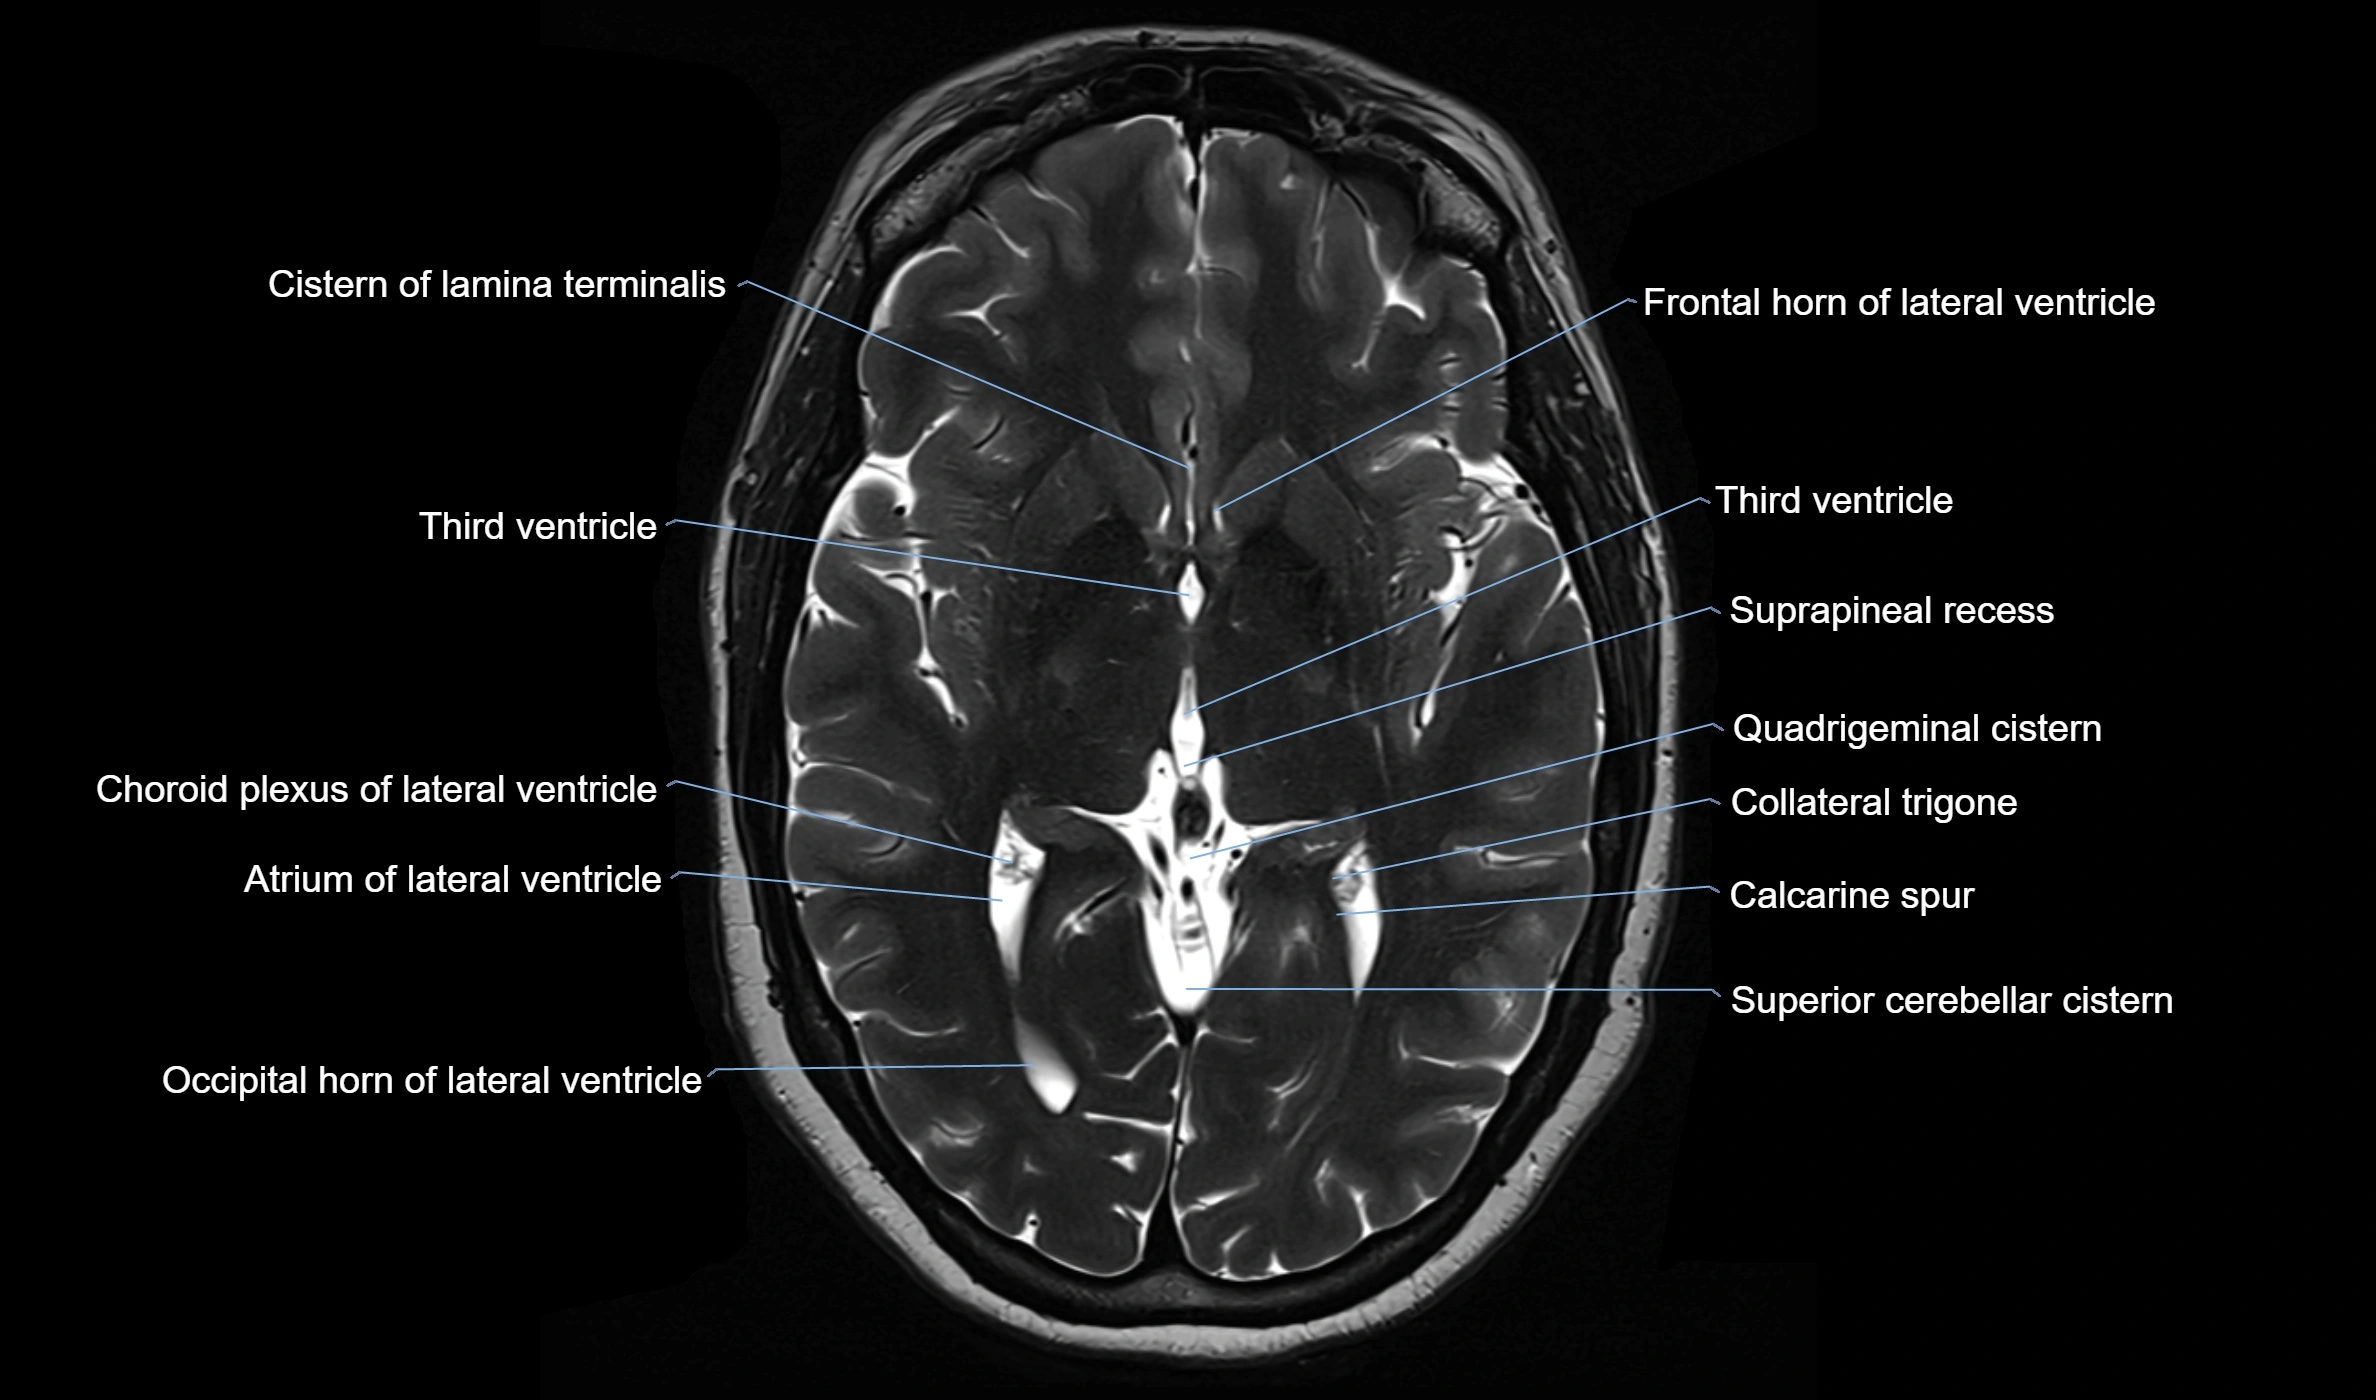

MRI images

image